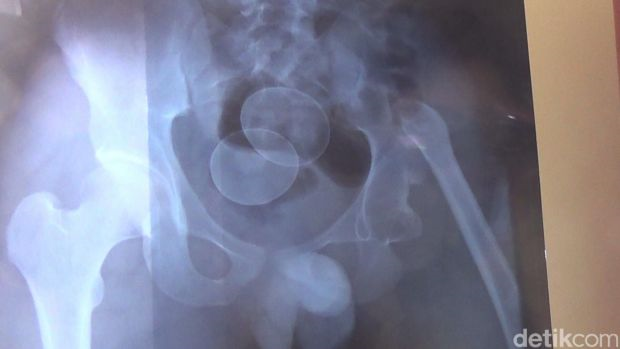

Pada masa itu, pakar perubatan bingung melihat kewujudan objek yang bentuk dan saiznya sama seperti telur ayam 'bersarang' dalam rektumnya (dubur) dan tidak ada penjelasan diberikan mengenai dakwaan yang dibuat terhadap telur-telur itu.

Jurucakap hospital Muhammad Taslim mencurigai telur yang berada dalam tubuh Akmal sengaja dimasukkan sendiri.

Ini kerana, katanya, mengikut logik perubatan adalah mustahil untuk telur itu berada di saluran pencernaan.

"Secara ilmiah tidak mungkin ada telur di dalam tubuh manusia. Itu tidak mungkin, apatah lagi di saluran pencernaan," katanya.